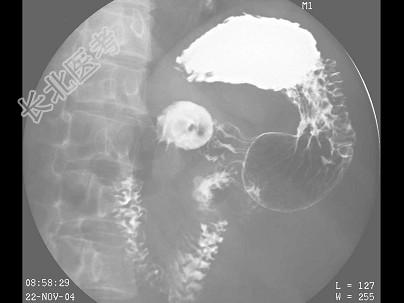

- 多项选择题女,49岁, 进食上腹痛,腹部肠胀气近2天, 今肛门已排气,大便已解, 结合图像,最可能的诊断为 ( )

C、胃溃疡

D、球部溃疡

E、胃粘膜脱垂